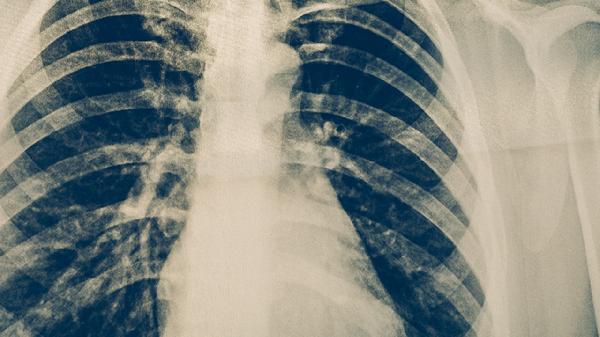

卡介菌多糖核酸注射液通过激活单核-巨噬细胞系统增强非特异性免疫,适用于慢性纤维空洞型肺结核。需肌内注射,常见注射部位硬结反应。治疗期间应定期复查胸片,避免与其他疫苗同时接种。活动性结核病患者禁用。